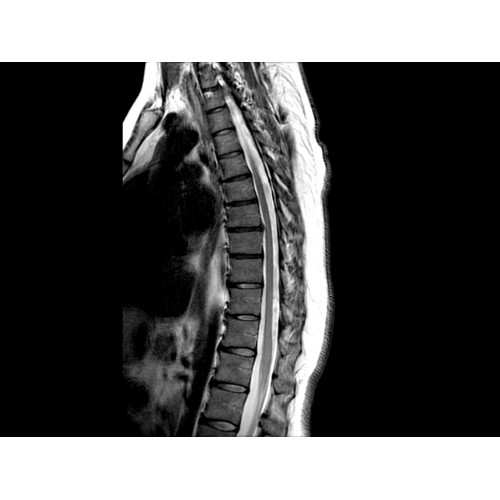

• Визуализация всего позвоночника слиянием двух участков — получить изображение всего позвоночника можно намного быстрее.

• Широкое поле зрения — поле зрения шириной 50 см позволяет охватывать крупные анатомические области за меньшее число сканов.